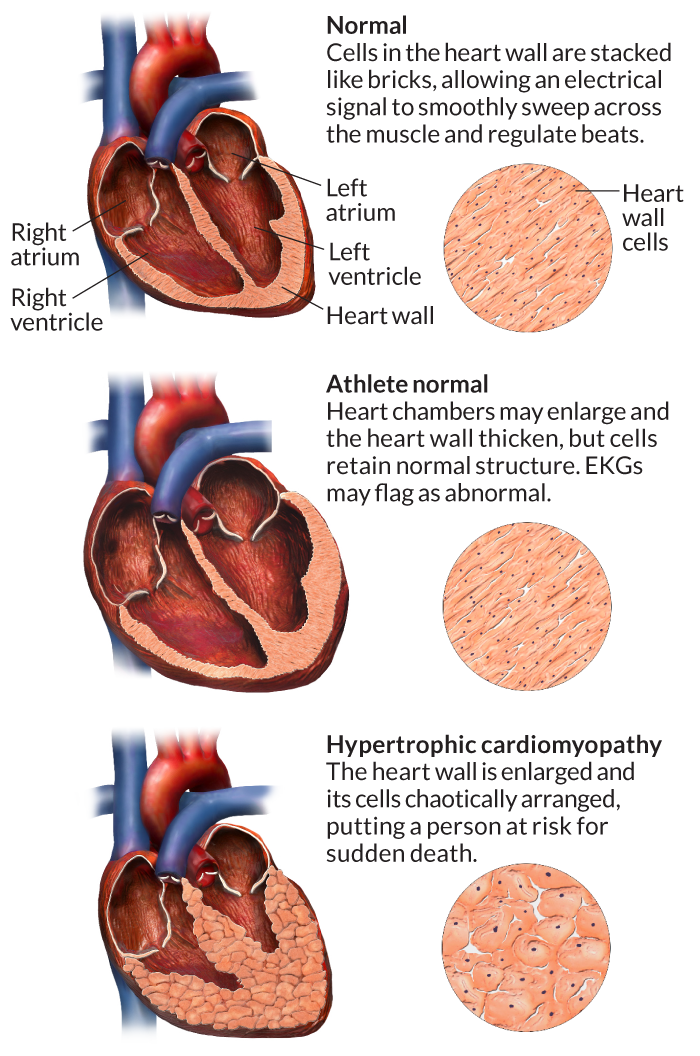

Sudden Cardiac Death In Young Athletes – Howard J. Luks, MD

www.howardluksmd.comSudden cardiac death in young athletes – Howard J. Luks, MD

www.howardluksmd.comSudden cardiac death in young athletes – Howard J. Luks, MD

Mechanism Behind Sudden Cardiac Deaths In Sports Uncovered | University

www.ox.ac.ukMechanism behind sudden cardiac deaths in sports uncovered | University …